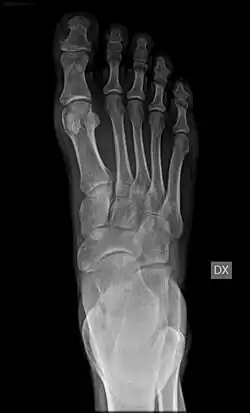

Em anatomia, denomina-se metatarso a parte mediana do pé, nos membros posteriores (ou extremidades inferiores,[1] no ser humano) dos mamíferos e outros vertebrados. É formado pelos cinco ossos metatarsais, que articulam com o tarso pelas suas extremidades proximais e com as primeiras falanges pelas extremidades distais.

Esta secção do esqueleto é correspondente ao metacarpo dos membros anteriores (ou extremidades superiores, no ser humano) - as mãos.